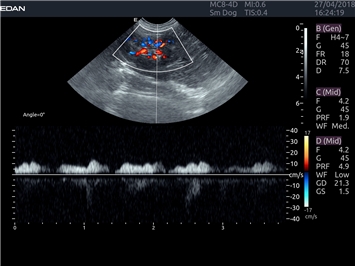

EDAN Acclarix LX4 VET

EDAN Acclarix LX4 VET представляет собой профессиональную ультразвуковую систему, специально разработанную для ветеринарных исследований. Сочетание стабильности, высокой производительности и эффективности делает эту систему идеальным выбором для современной ветеринарной практики.

Импульсно-волновой допплер:

Да

Триплексное сканирование: